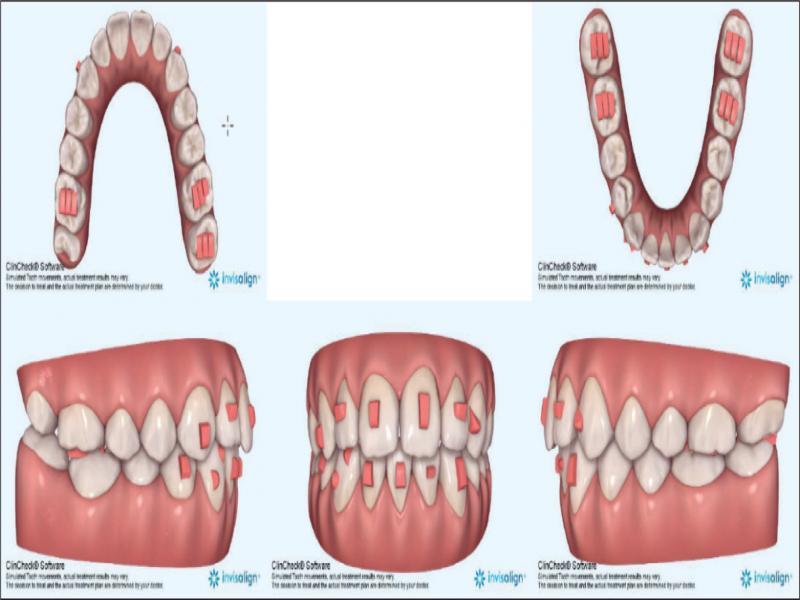

With these considerations, it was planned to treat the patient by the extraction of the lower right central incisor (41), by transverse dental arch expansion, and the management of the vertical relationships by avoiding mechanics that would tend to extrude posterior teeth. The 41 was chosen for extraction as it allowed for alignment of the remaining lower incisors, largely through mesial crown tip. In addition, there was slightly less gingival attachment on 41 and the tooth had a small incisal fracture. The extraction of 31 would perhaps have been more advantageous for the alignment of 32 but would have necessitated a more challenging bodily translation of 41 rather than mainly mesial crown tip. It was considered that clear aligner therapy would be beneficial from a vertical perspective, by minimising the extrusive mechanics inherent to fixed appliances. Figure 4 shows the prescribed finishing position of the dentition. Vertical control was augmented by the placement of occlusal bite pads in the aligners themselves on the occlusal of the molars in both arches to provide a bite-plane effect posteriorly (Figure 5). Furthermore, the absence of fixed appliances serving as a predisposing factor is favourable in managing concerns regarding the patient’s oral hygiene and cariogenic dietary intake.

Invisalign® predicted outcome showing attachments.